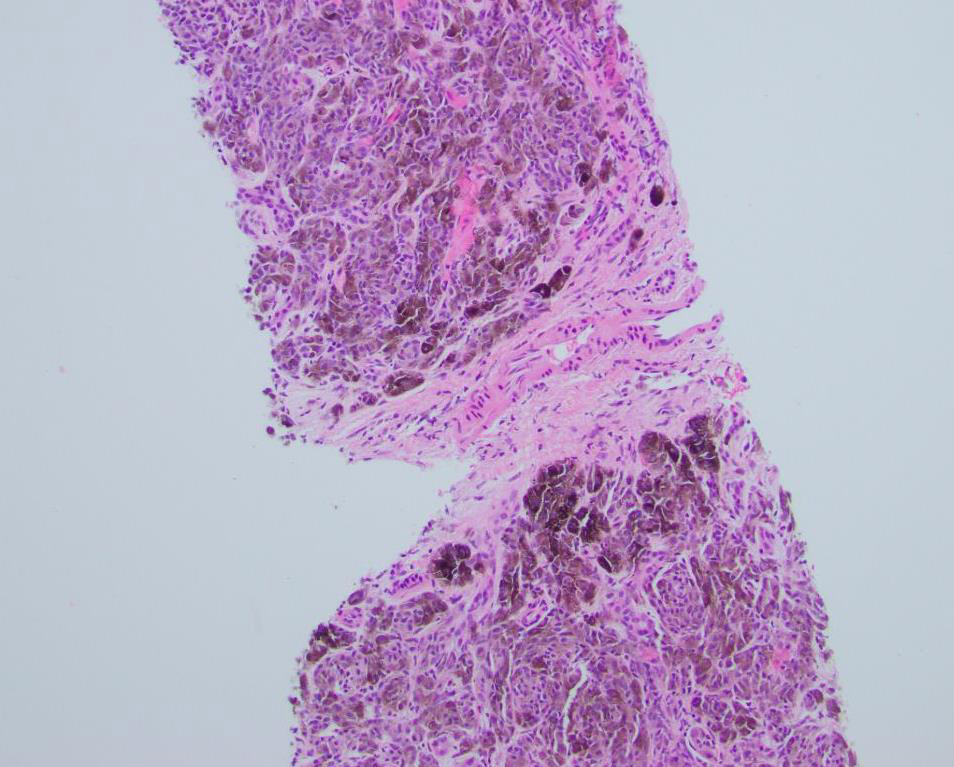

The patient underwent an abdominal ultrasound which revealed multiple hypoechoic lesions less than 1 cm dispersed throughout the liver (Figure 1). Magnetic resonance imaging was also performed and demonstrated multiple lesions dispersed throughout the liver (Figure 2). In addition, both imaging modalities showed a background of hepatic steatosis. Biopsy of a representative liver lesion demonstrated a malignant neoplasm infiltrating the hepatic parenchyma arranged primarily in a nested pattern (Figure 3). The neoplasm was composed of spindled and epithelioid cells with deep brown pigmentation within the cytoplasm (Figures 4 and 5). Given the morphologic findings, no immunohistochemical studies were performed.